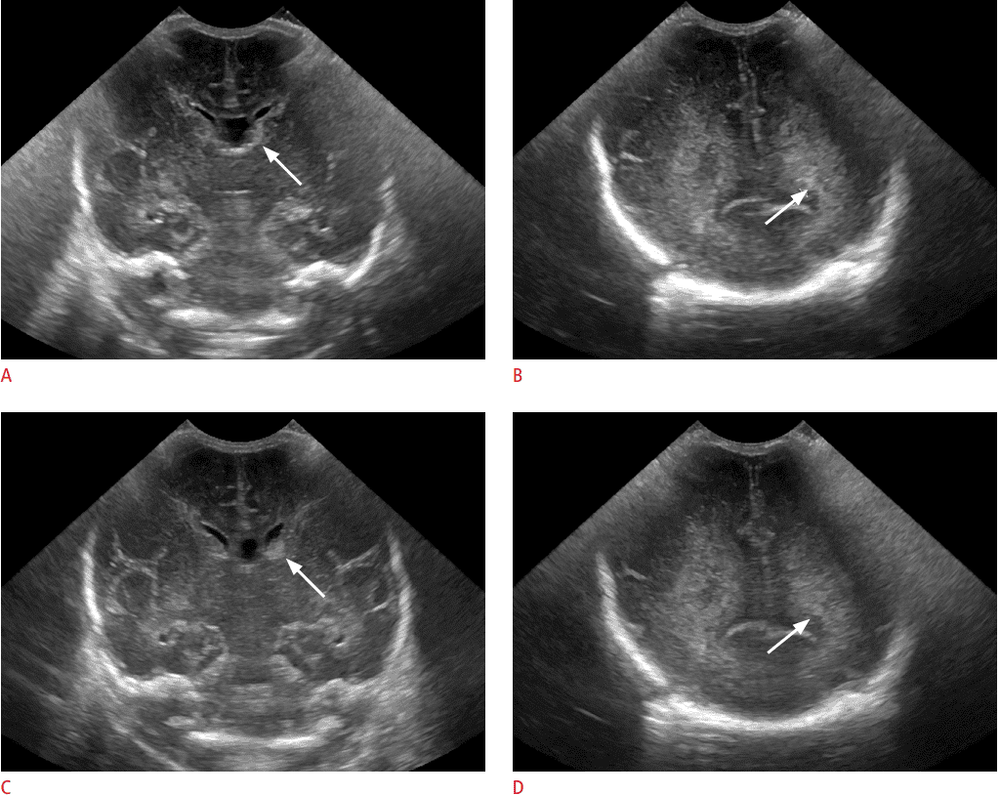

Hình ảnh kết quả siêu âm qua thóp trẻ sơ sinh